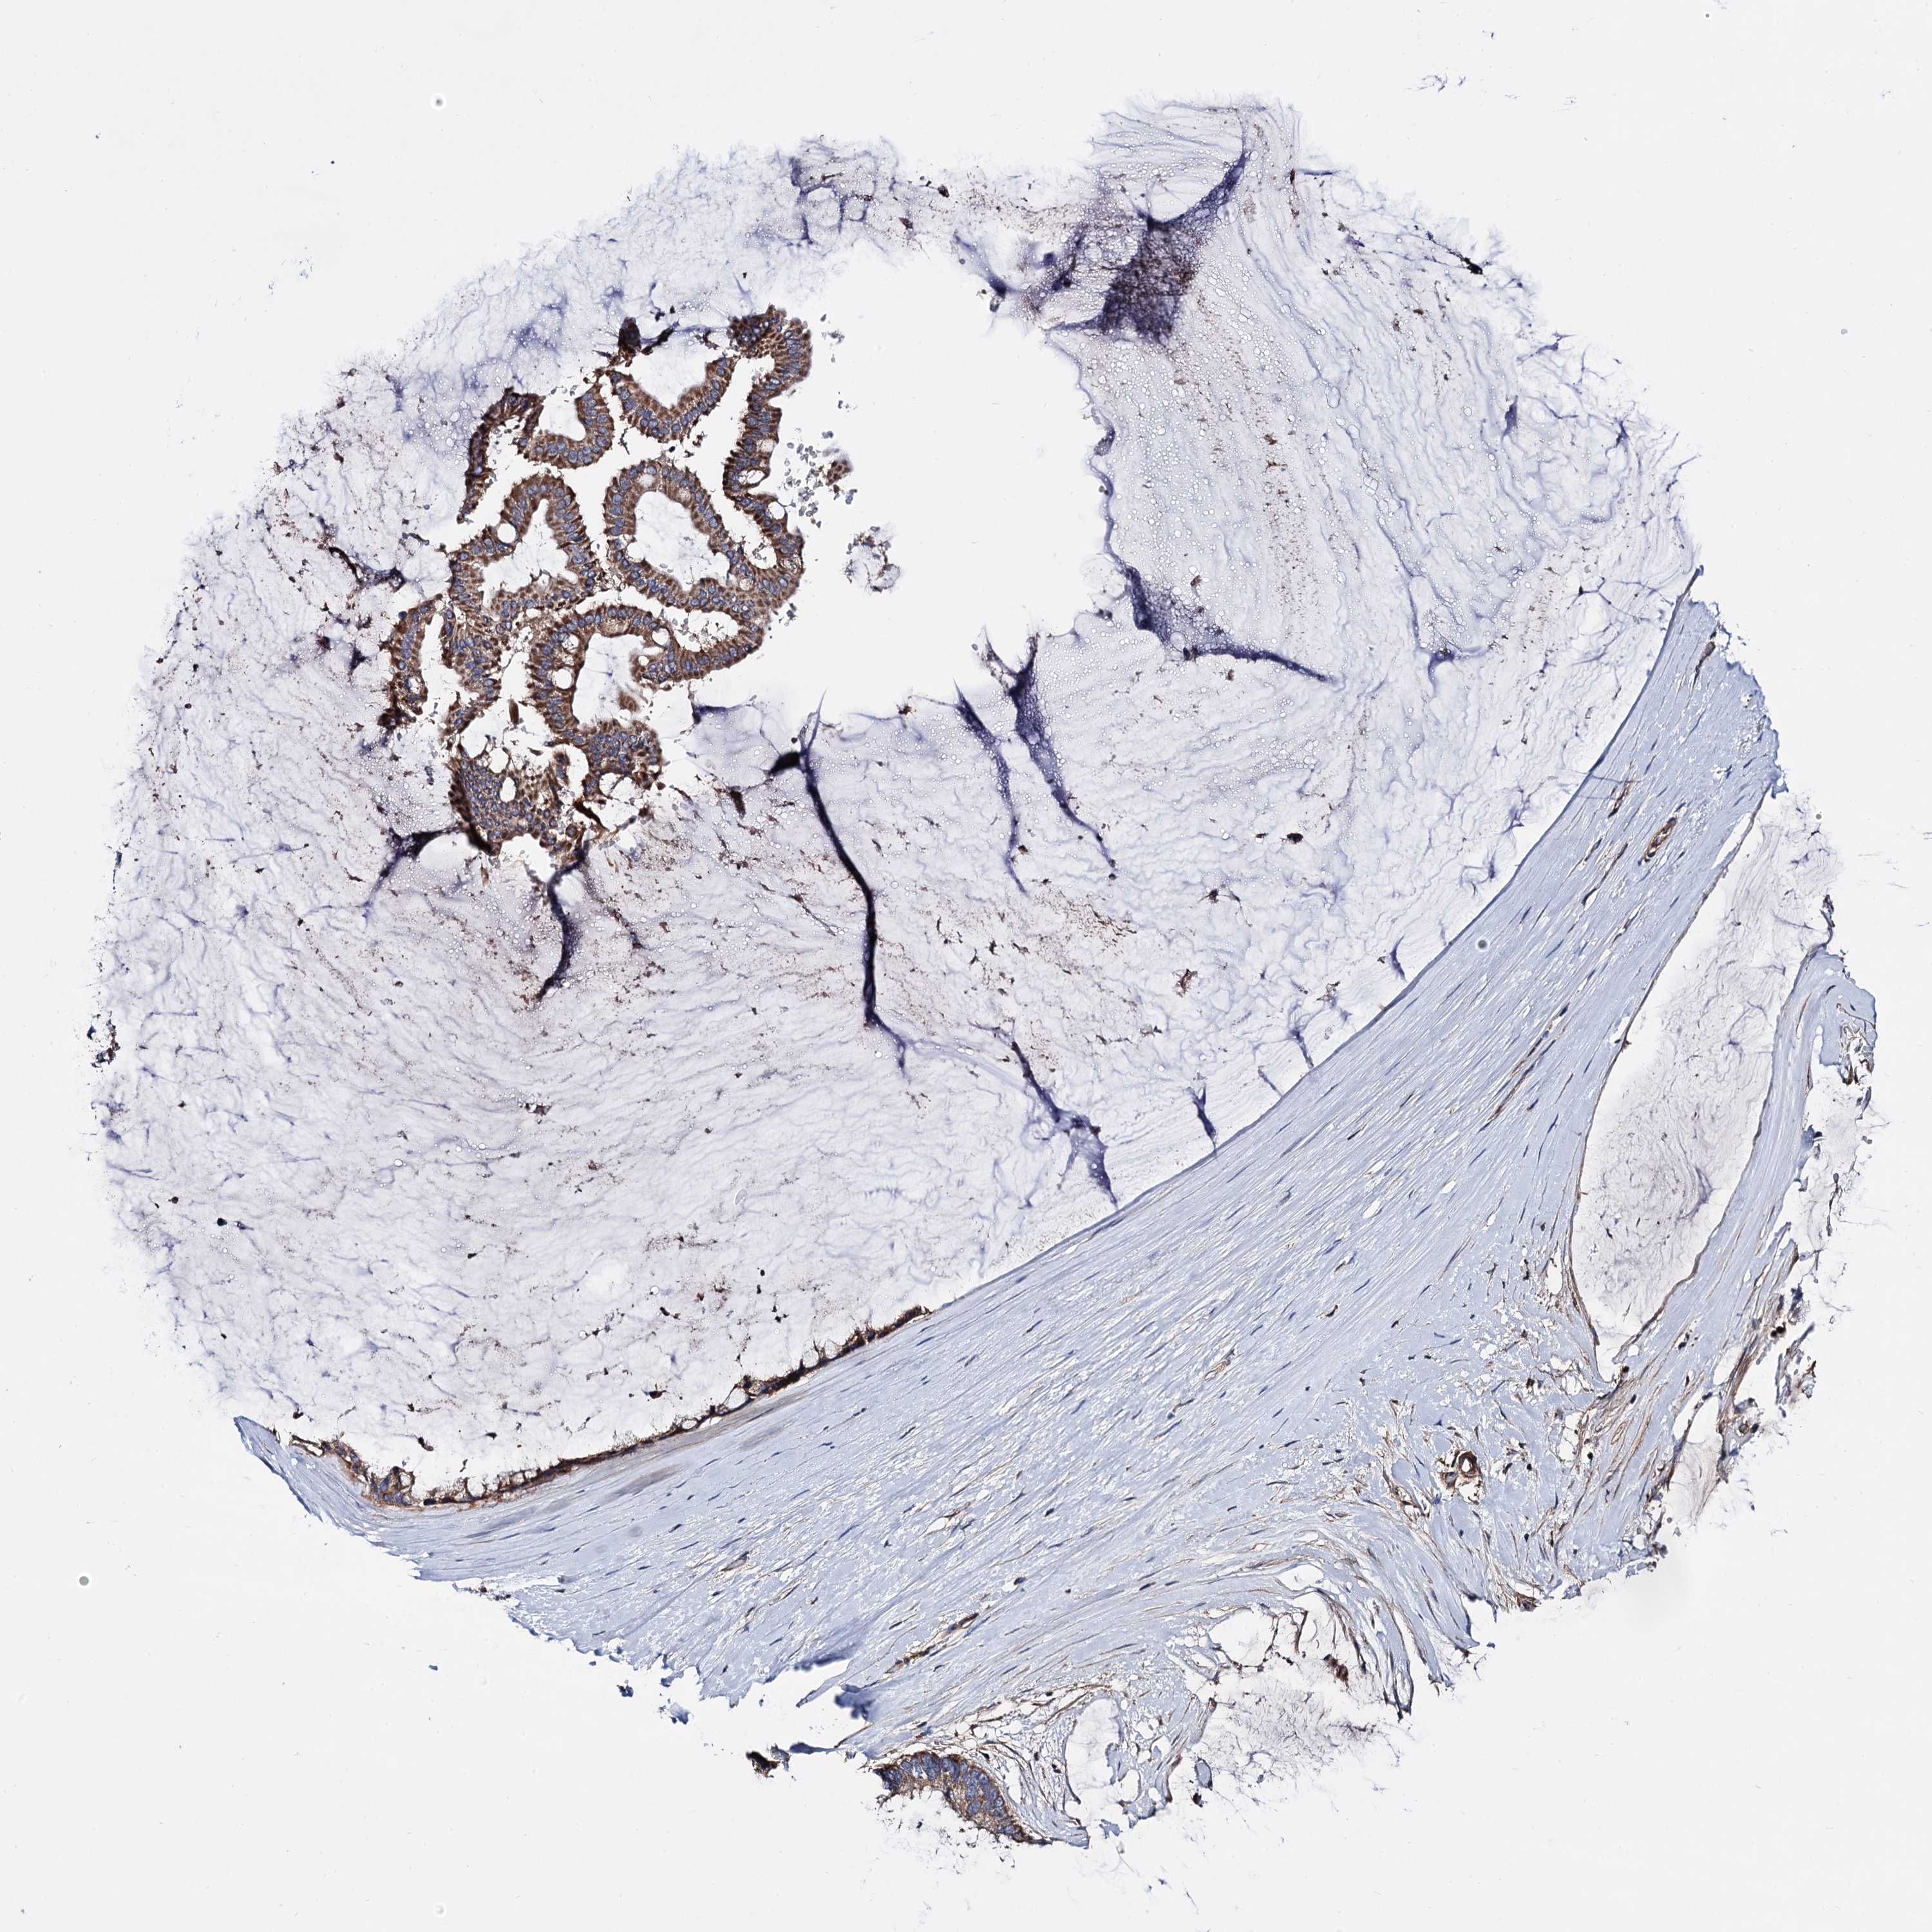

OVARIAN CANCER - Protein expressioni

A mouse-over function shows sample information and annotation data. Click on an image to view it in a full screen mode. Samples can be filtered based on level of antibody staining by selecting one or several of the following categories: high, medium, low and not detected. The assay and annotation is described here.

Note that samples used for immunohistochemistry by the Human Protein Atlas do not correspond to samples in the TCGA dataset.

Antibody stainingi

Antibody staining in the annotated cell types in the current human tissue is reported as not detected, low, medium, or high, based on conventional immunohistochemistry profiling in selected tissues. This score is based on the combination of the staining intensity and fraction of stained cells.

Each image is clickable and will lead to virtual microscopy that enables deeper exploration of all samples and also displays staining intensity scores, fraction scores and subcellular localization as well as patient and tissue information for each sample.

Antibody HPA040845

Staining

High

Medium

Low

Not detected

Intensity

Strong

Moderate

Weak

Negative

Quantity

>75%

75%-25%

<25%

None

Location

Nuclear

Cytoplasmic/membranous

Cytoplasmic/membranous,nuclear

Cystadenocarcinoma, serous, NOS

Carcinoma, endometroid

Cystadenocarcinoma, mucinous, NOS

Carcinoma, NOS